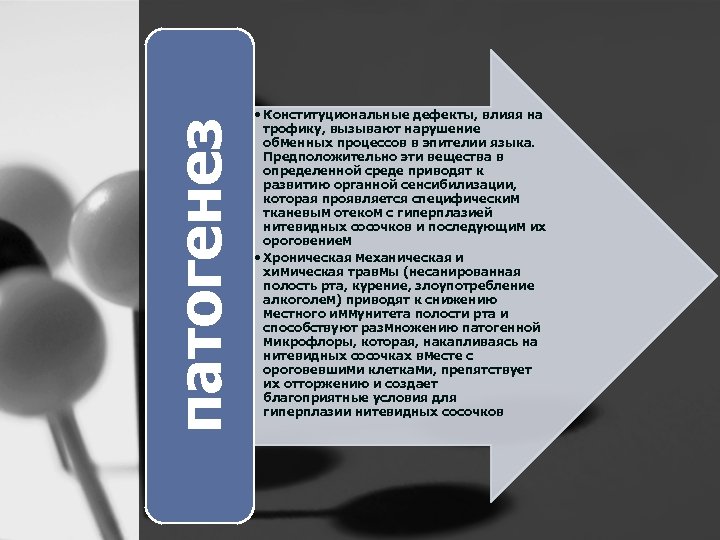

патогенез • Конституциональные дефекты, влияя на трофику, вызывают нарушение обменных процессов в эпителии языка. Предположительно эти вещества в определенной среде приводят к развитию органной сенсибилизации, которая проявляется специфическим тканевым отеком с гиперплазией нитевидных сосочков и последующим их ороговением • Хроническая механическая и химическая травмы (несанированная полость рта, курение, злоупотребление алкоголем) приводят к снижению местного иммунитета полости рта и способствуют размножению патогенной микрофлоры, которая, накапливаясь на нитевидных сосочках вместе с ороговевшими клетками, препятствует их отторжению и создает благоприятные условия для гиперплазии нитевидных сосочков